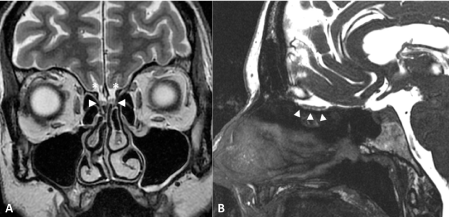

Figure 1: Normal olfactory bulbs.

MRI of normal-size olfactory bulbs (arrowheads) on coronal T2-weighted imaging (A) and sagittal Fast Imaging Employing Steady-state Acquisition, FIESTA (B). Olfactory sulci are well seen (star). View Figure 1